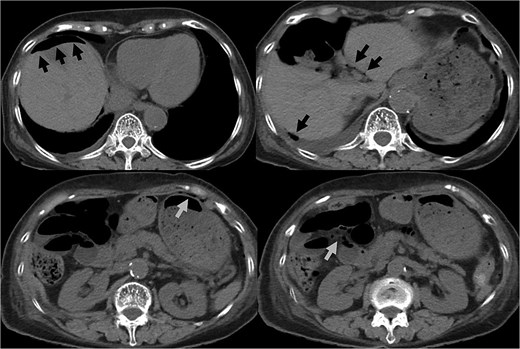

An 82-year-old female with a history of cervical carcinoma presented to our hospital with lower abdominal pain. She had undergone a total hysterectomy decades ago for cervical carcinoma, followed by radiotherapy to the pelvis. Computed tomography (CT) revealed small bowel obstruction attributable to adhesions. The patient was initially diagnosed with adhesion-related small bowel obstruction and was managed conservatively with fasting and intravenous fluid replacement. Although her bowel function promptly recovered within a few days, urinary retention of unknown etiology was noted during hospitalization, necessitating clean intermittent catheterization. When this approach proved insufficient for relieving her symptoms, an indwelling urinary bladder catheter was inserted. Two days after insertion of the catheter, a follow-up abdominal X-ray was performed to confirm recovery of her bowel movement. Imaging revealed indwelling intra-abdominal air above the liver, which was confirmed by emergency computed tomography, raising the suspicion of gastrointestinal perforation (Figs 1 and 2). Clinically, her vital signs were stable, with a heart rate of 65 beats per minute, blood pressure of 113/72 mmHg, and body temperature of 36.6°C, and her abdomen was soft and flat with slight tenderness in the lower abdomen. Laboratory evaluation indicated a C-reactive protein level of 2.31 mg/dl and leukocytes of 5100/mm3. Emergency laparotomy was performed under general anesthesia to rule out potentially life-threatening conditions, such as gastrointestinal perforation. Intra-operatively, perforation of the urinary bladder was identified, with the urinary catheter protruding through the defect (Fig. 3). The bladder wall was extremely thin and fragile, suggesting significant loss of compliance. The bladder rupture was repaired using a two-layer closure with absorbable sutures, and the urinary catheter was repositioned to ensure proper drainage. The patient’s postoperative recovery was uneventful, and she was discharged on postoperative day 25 with the urinary catheter in situ. She was followed up for 70 days, and no signs of intra-abdominal leakage were observed on cystography. The catheter was removed without further complications.

CT indicated intra-abdominal free air (arrows). These findings were later confirmed as being due to bladder rupture.